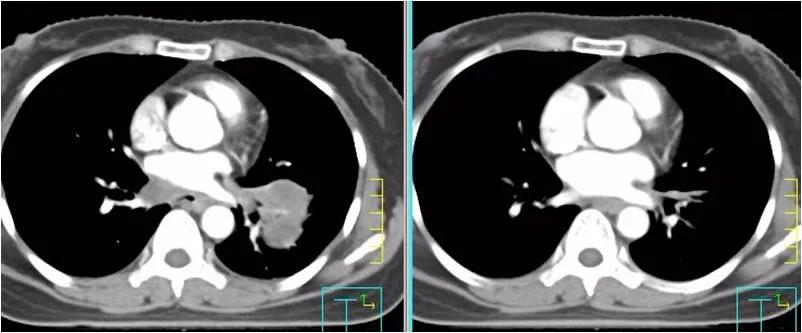

疗效评价:纵膈淋巴结及肺部转移灶均明显缩小,疗效达PR。血肿瘤指标SCC由218ng/ml下降到2.99 ng/ml。患者咳嗽、胸闷症状明显缓解。

左图为:2020-09-02治疗前 ,右图为2020-10-14两周期治疗后